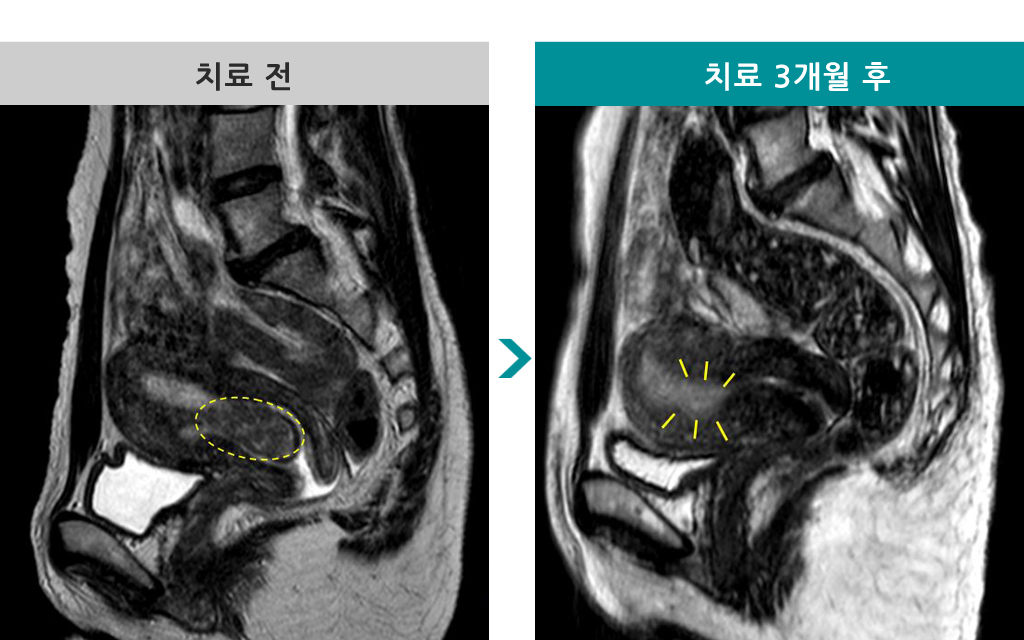

40세 [자궁근종 MR하이푸] 전후 MRI사진 비교

[자궁근종 MR하이푸] 전후 MRI사진 비교

▶ 주치의 : 김영선 원장

▶ 환자 : 40세 여성

▶ 자궁근종의 종류와 크기 : 4cmx2cm 자궁근종

▶ 자궁근종으로 인한 불편증상 : 리과다, 생리통

▶ 치료 경과 : MR하이푸 시술 후 사이즈 축소. 생리양 10->5, 생리통 사라짐, 증상점수 32점 → 20점.